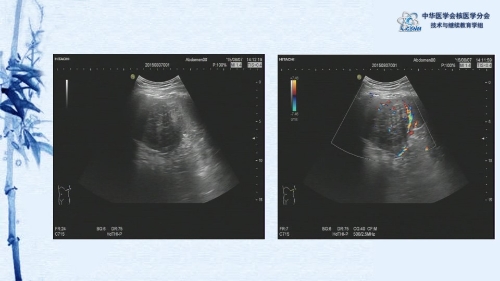

【CSNM继教学组】病例E9-邢岩:脾脏硬化性血管瘤样结节性转化